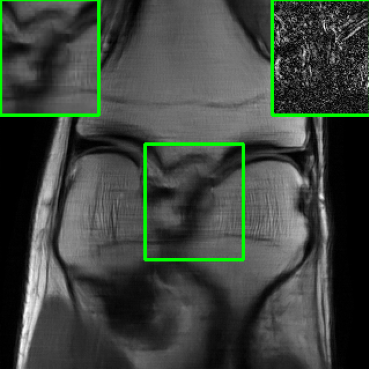

| Ground Truth | Vanilla MoDL | RS-E2E | SMUG |

![]() |

| PSNR = dB | PSNR = 21.48 dB | PSNR = 23.09 dB | PSNR = 26.51 dB |

| AT | Score-MRI | Deep-Equilibrium | Weighted-SMUG |

| PSNR = 26.34 dB | PSNR = 25.78 dB | PSNR = 21.32 dB | PSNR = 26.89 dB |

Results for the FastMRI Knee Dataset: In Fig 5 and Fig 7, we report PSNR and SSIM results of different methods at two sampling acceleration factors for the knee dataset. Therein, we observe quite similar outcomes to those reported in Fig 3. Figs. 6 and 8 show reconstructed images by different methods for knee scans at 4x and 8x undersampling, respectively. We observe that SMUG and Weighted SMUG show fewer artifacts, sharper features, and fewer errors when compared to Vanilla MoDL and other baselines in the presence of the worst-case perturbations.